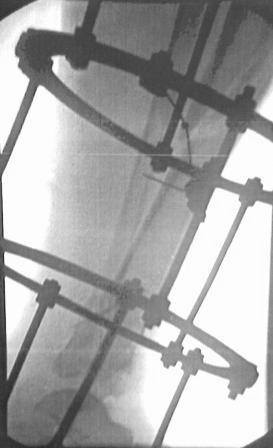

Открытый перелом 43.С3.3

Больной 41г переведен из ЦРБ, травма в результате ДТП- 5 дней назад, произведена ПХО раны, наложена гипсовая повязка.

Об-но; начиная с с/з голени продольно - почти циркулярная рана, с признаками инфицирования - покраснение, отечность, усиление боли, местная т-ра и мутные кровянистые выделения из раны, и выраженная деформация голени. В отд нашей коллегой в экстренном порядке в задней поверхности голени щвы распушены, выпушено около 50мл мутной гематомы, АВФ, умеренная дистракция, антибиотики, и т.д.

Наш план; после устранения воспалительных процессов, перемонтаж аппарата, репозиция оставшихся смещений спицами с упорной плошадкой и стабилизация аппарата, дальше по обстановке.